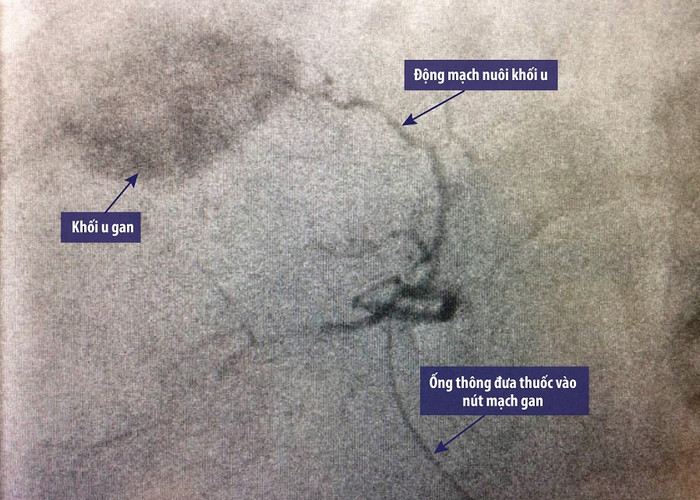

| Hình ảnh khối u gan được bơm thuốc nút mạch dưới hướng dẫn DSA. |

Bác sĩ Nguyễn Văn Phấn, Khoa Chẩn đoán hình ảnh (Bệnh viện Vinmec Times City) cho biết: “Trong khoảng 2h-3h, bệnh nhân được đặt 1 ống thông từ động mạch đùi phải, luồn vào các nhánh động mạch nuôi khối u để bơm dung dịch Lipiodol và hóa chất, gây tắc hoàn toàn các mạch máu nuôi khối u.

Quá trình nút mạch được thực hiện trong phòng chụp mạch DSA nên có thể nhìn rõ các nhánh mạch máu đi vào khối u, cho phép tiếp cận khối u gần nhất và chính xác nhất”.